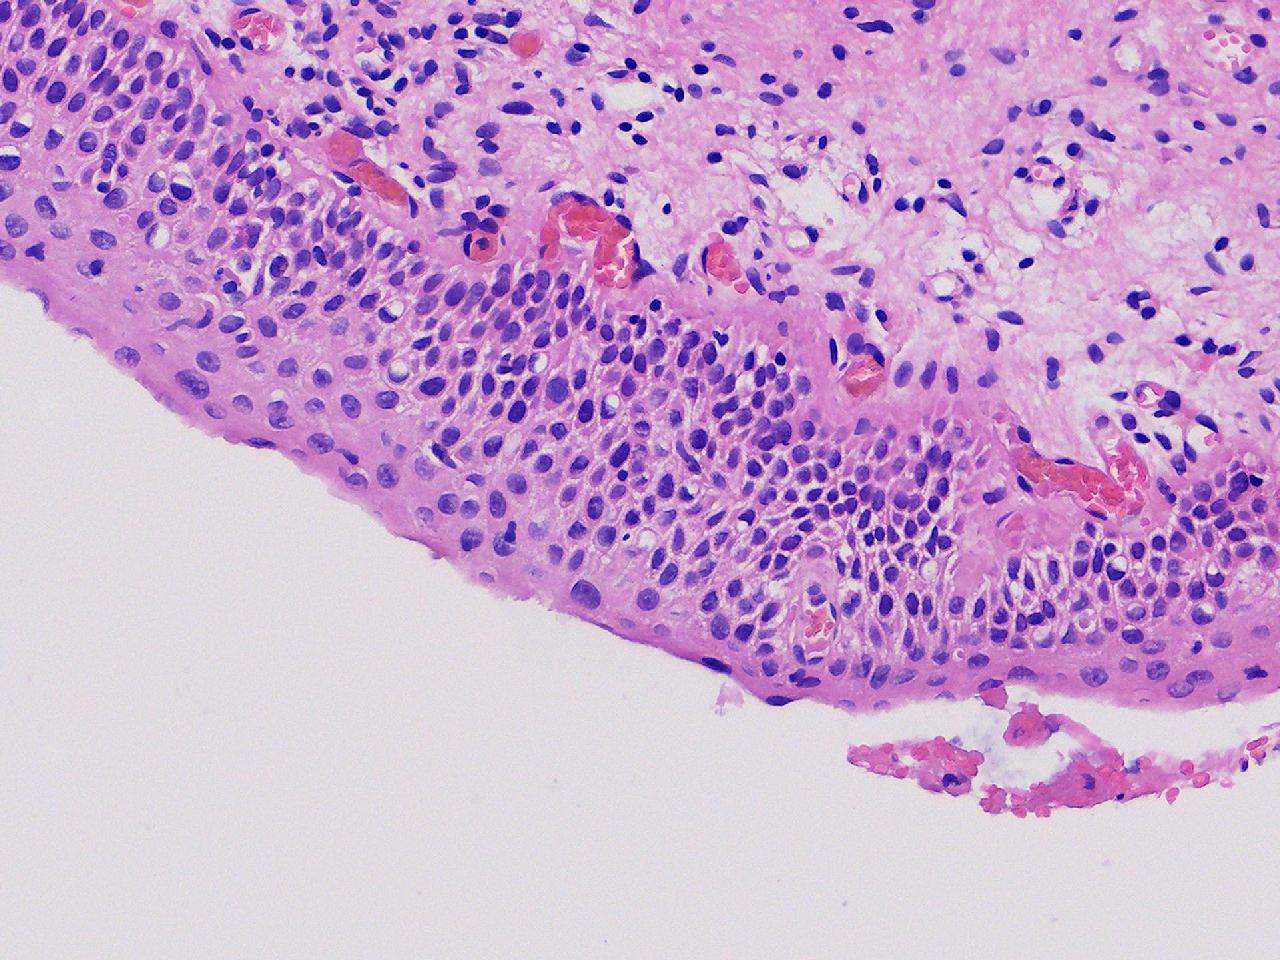

CIN1级? CIN2级?

性别年龄61岁临床诊断

一般病史女,61岁,宫颈活检,,HPV6+ 52+

标本名称宫颈活检

大体所见灰白色不整形软组织1块,直径0.3厘米。

CIN2倒是不够,图3有几个像挖空细胞,HPV有阳,勉强可以考虑小灶LSIL。

• zhuang xia nan:  是的。  2级肯定不够,有挖空细胞,小灶1级。    谢谢老师指点。

CIN1.